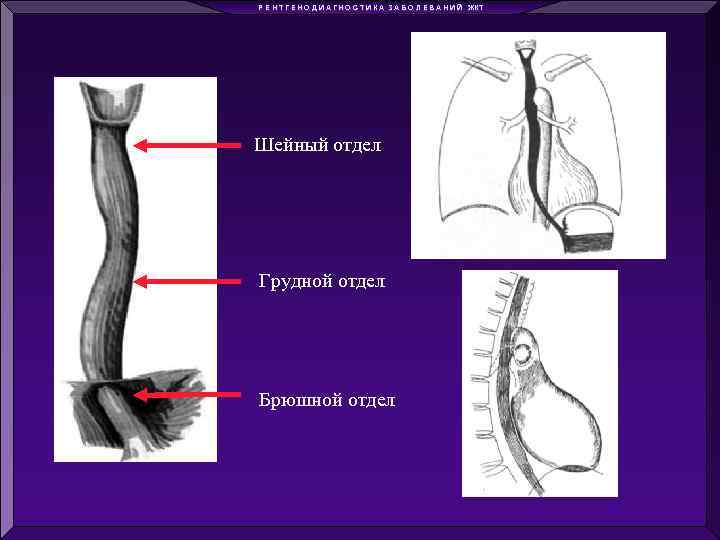

Р Е Н Т Г Е Н О Д И А Г Н О С Т И К А З А Б О Л Е В А Н И Й ЖКТ Шейный отдел Грудной отдел Брюшной отдел

Р Е Н Т Г Е Н О Д И А Г Н О С Т И К А З А Б О Л Е В А Н И Й ЖКТ Шейный отдел Грудной отдел Брюшной отдел